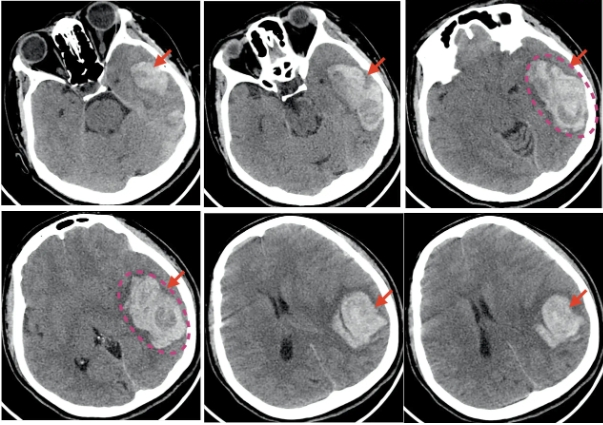

CT检查(计算机断层扫描)

CT利用X射线束对人体进行多层扫描,通过计算机重建出三维图像,提供更详细的解剖信息。

1.高分辨率三维图像:可以清晰地显示器官、血管、骨骼的细节。

●肿瘤诊断:如肺癌、肝癌、脑瘤等的早期发现和分期。

●头部检查:如脑出血、脑梗死、颅内肿瘤等。

●精准诊断:CT能够提供更详细的影像信息,帮助医生明确病变的性质、范围和严重程度。

●治疗指导:在手术前或放疗前,CT可以为医生提供精确的解剖信息,辅助制定治疗方案。

●疾病监测:用于肿瘤、血管病变等疾病的随访和疗效评估。